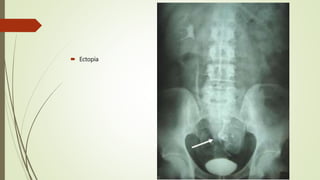

 Ectopia